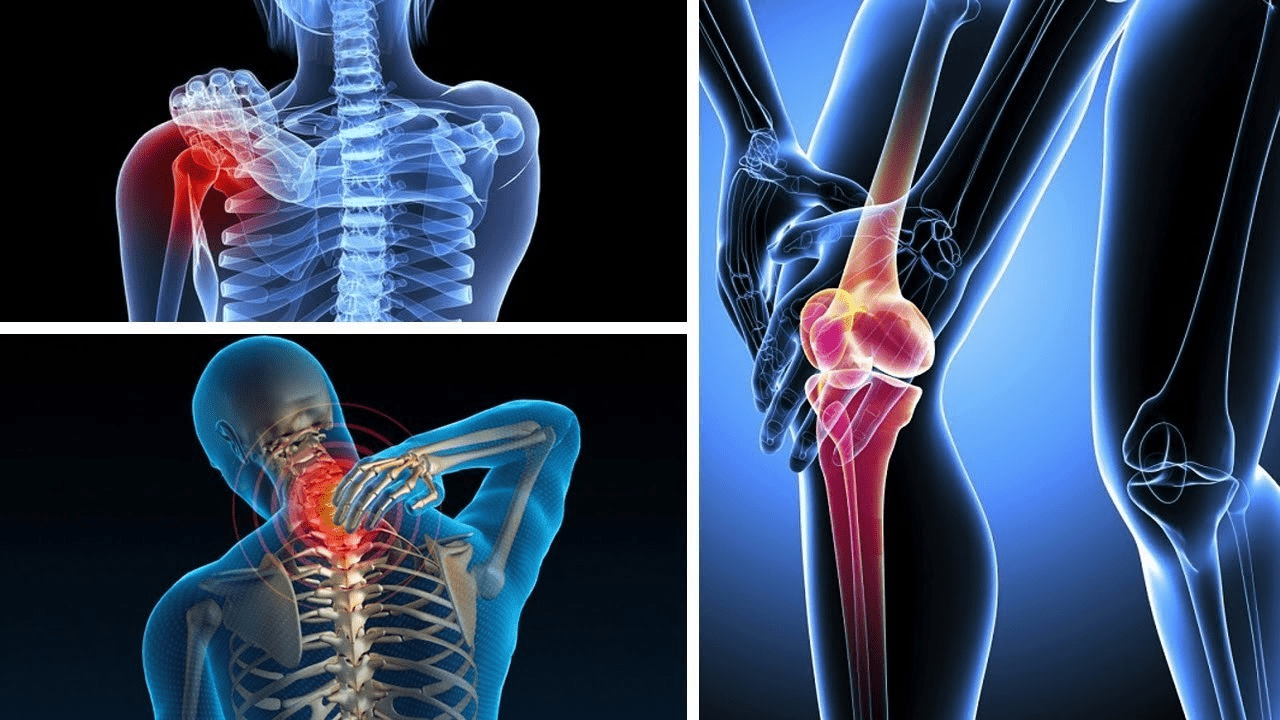

Did you know that over 32 million American adults are living with osteoarthritis, and nearly 1 in 4 adults over age 55 report regular knee pain that steals their freedom to move? That statistic hits hard when it’s your own mother, father, or even you staring at the stairs you once bounded up without a second thought.

Turning 50 often feels like flipping a switch. One day you’re chasing dreams; the next, your knees protest every bend. According to recent health data, 70% of adults aged 50-80 experience ongoing joint pain, with women facing even higher odds after menopause. It’s not just “getting older”—it’s wear-and-tear on cartilage, creeping inflammation, and reduced natural cushioning that turns everyday movements into ordeals.

Pause for 10 seconds: Picture your biggest frustration right now. Is it struggling to stand after sitting? Or the way swelling makes your knees feel twice their size by evening? You’re not alone—and it’s not your fault. But here’s the brutal truth: Ignoring it leads to a vicious cycle. Less movement means weaker muscles, which means more pressure on already-stressed joints. Before you know it, independence slips away.